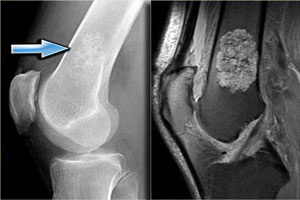

- рентгенографии — на рентгеновских снимках четко определяется новообразование, отображается ряд его особенностей;

- КТ, МРТ — высокоточные методы, показанные для исследования неоплазий, развившихся в плечевых и тазовых костях, позвоночнике, позволяют на любой стадии развития опухоли получить подробную информацию о ее структуре, темпах роста;